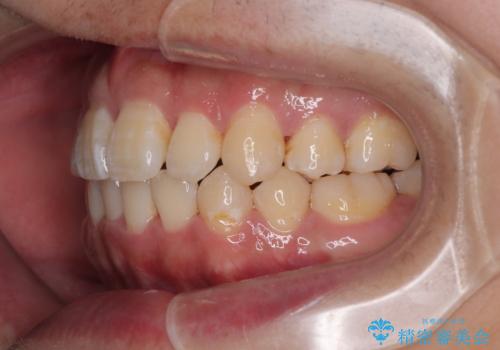

前歯のデコボコを抜歯矯正で改善した症例|目立ちにくい審美装置を使用

矯正中の見た目を気にされていたため、プラスチックブラケット+コーティングワイヤーを使用した、目立ちにくい審美矯正装置を選択しました。

矯正治療では、見た目だけでなく清掃性が向上し、将来的なむし歯や歯周病リスクを下げることが可能です。